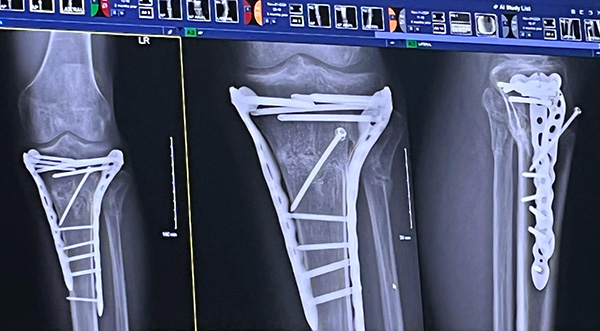

Among his injuries are tibia and fibula fractures, a fractured tibia plateau, and bulging C3 and C4 disks in his neck. He has already undergone one surgery, with at least one more expected in the near future.